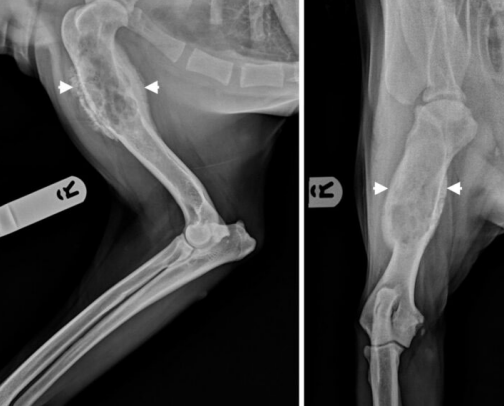

- Osteosarcoma (골육종) : 개에서 가장 흔한 malignant bone tumor.

- 긴뼈의 metaphysis 부위, 대형견에서 잘 발생함.

- 뼈의 융해와 생성을 유발, locally aggresive, 흔히 전이됨.